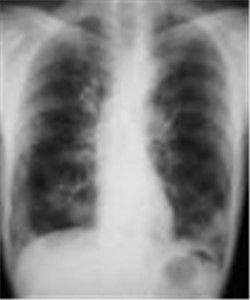

胸部X線表現為從兩側肺門向外放散的彌散性邊緣模糊細小結節陰影,常融合成片狀,病灶之間有代償性氣腫或形成小透亮區。

(1)X線檢查典型X線胸片可見肺門周圍細小瀰漫性羽毛狀浸潤陰影,從肺門向肺邊緣擴散,呈蝴蝶狀,略似肺水腫;或表現為軟狀低密度的結節狀陰影,呈蝶形分布。有時兩肺下葉顯示浸潤性病變,或有些患者開始時呈結節狀密度增深影,從兩下葉浸潤進展為整個大葉實變。病灶之間有代償性肺氣腫或形成小透亮區。縱隔明顯增寬,X線酷像肺水腫,但無K-B線。(2)胸部CT檢查尤其是高分辨CT對PAP有很大診斷價值。病變肺組織常呈毛玻璃樣改變,葉間葉內胸膜增厚而不規則。